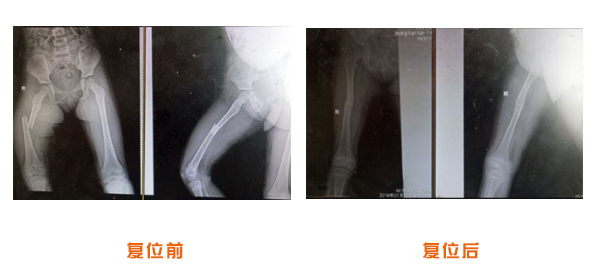

肥城市安駕莊梁氏骨科醫(yī)院是一所以梁氏手法正骨配合膏藥為特色的現代化??漆t(yī)院。

梁氏骨科術始創(chuàng)于清雍正年間,歷經八代,至今已有三百年歷史。據1929年泰安縣志載“梁瑞圖先生,字增生,號蓮峰,安駕莊人,精岐黃并發(fā)明接骨,凡跌打車凡跌打車軋皮不破而碎骨者......【詳細】 |